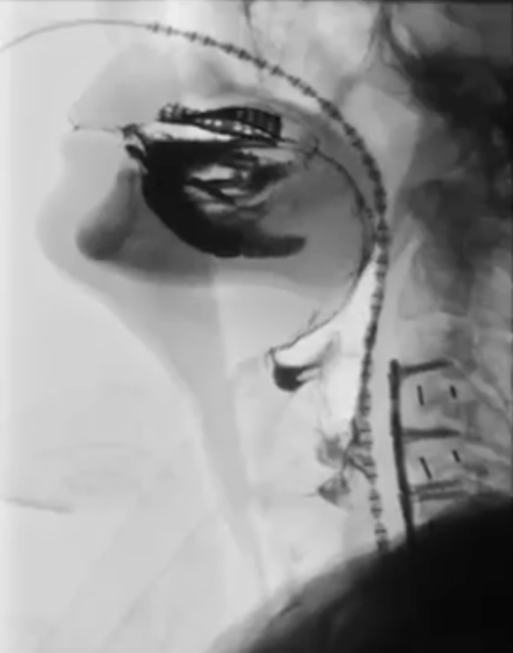

1.螢光透視吞嚥攝影(Videofluoroscopic Swallowing Study, VFSS)

在X光下吞入混入顯影劑(常用的是鋇劑)各種質地的食物,觀察食物自口腔、咽喉到食道,是否誤入氣管、是否殘留,此一檢驗是診斷與調整飲食質地的黃金標準。

優點:可以非常清楚地看到食物是否掉入呼吸道,或是否有食物殘留在咽喉。

限制:需要與影像科配合,排程時間可能較久。

圖說:螢光透視吞嚥攝影(照片提供/楊舒媚醫師)